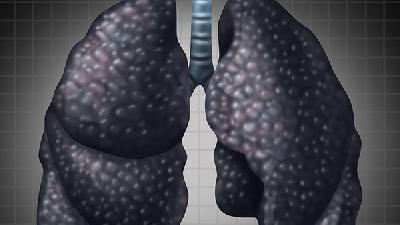

肺气肿的病因是什么

相信很多人都不是很了解肺气肿,肺气肿的危害其实是很大的,所以患者朋友一定要多加了解,肺气肿是一种肺部慢性病造成的一种疾病,结果造成肺的过度膨胀,与哮喘一并被列为一种慢性阻塞性肺病,患者需要对肺气肿的病因进行了解。1、感染:感染是肺气肿的病因中最值得注意的因素之一。病毒、细菌和支原体是本病急性加重的重要因素。病毒主要为流感病毒、鼻病毒、腺病毒和呼吸道合胞病毒等...

引起肺气肿的原因

肺气肿是指终末细支气管远端的气道弹性减退,过度膨胀、充气和肺容积增大或同时伴有气道壁破坏的病理状态,按其发病原因肺气肿有如下几种类型:老年性肺气肿、代偿性肺气肿、间质性肺气肿、灶性肺气肿、旁间隔性肺气肿、阻塞性肺气肿,下面我们给大家详细介绍一下引起肺气肿的原因。肺气肿的发病机制尚未完全清楚。一般认为与支气管阻塞以及蛋白酶-抗蛋白酶失衡有关。吸烟、感染和大气污...

老人肺气肿的致病因素

生活中发现有许多的老人患有肺气肿,肺气肿是肺部长期慢性危害形成的,如慢性支气管,气管炎等等都会转变成肺气肿,因此对于慢性气管炎的治疗也应该引起注意,千万不要再抽烟,或者在环境恶劣的条件下长期的工作,平时尽量减少呼吸道疾病的感染,那么,老人肺气肿的致病因素有哪些呢?1、感染呼吸道病毒和细菌感染与肺气肿的发生有一定关系。反复感染可引起支气管粘膜充血、水肿,腺体增...